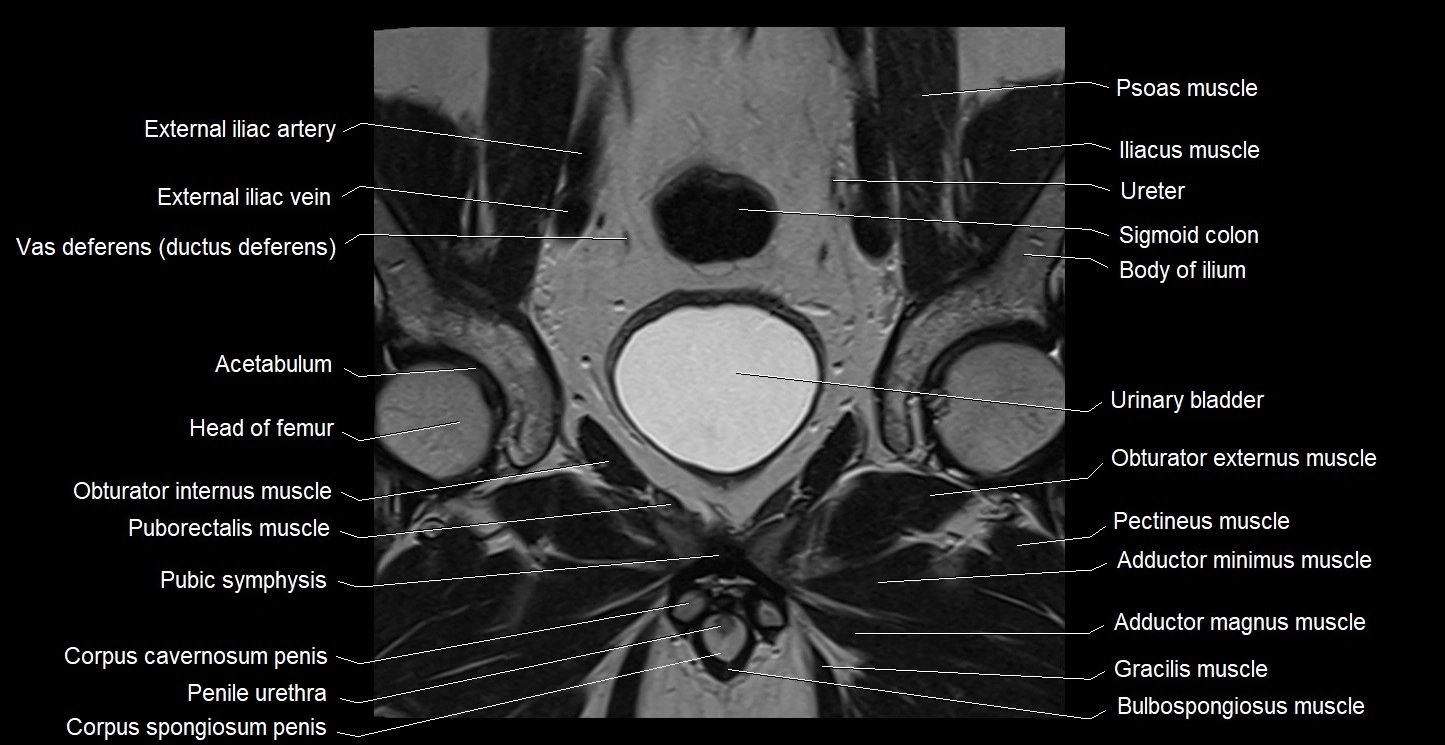

- Acetabulum

- Body of ilium

- Bulbospongiosus muscle (Male)

- Gracilis muscle

- Head of femur

- Obturator externus muscle

- Obturator internus muscle

- Pectineus muscle

- Pubic symphysis

- Puborectalis muscle

- Urinary bladder